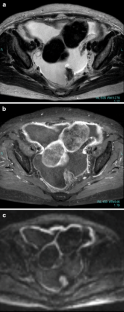

Fig. 10a–c